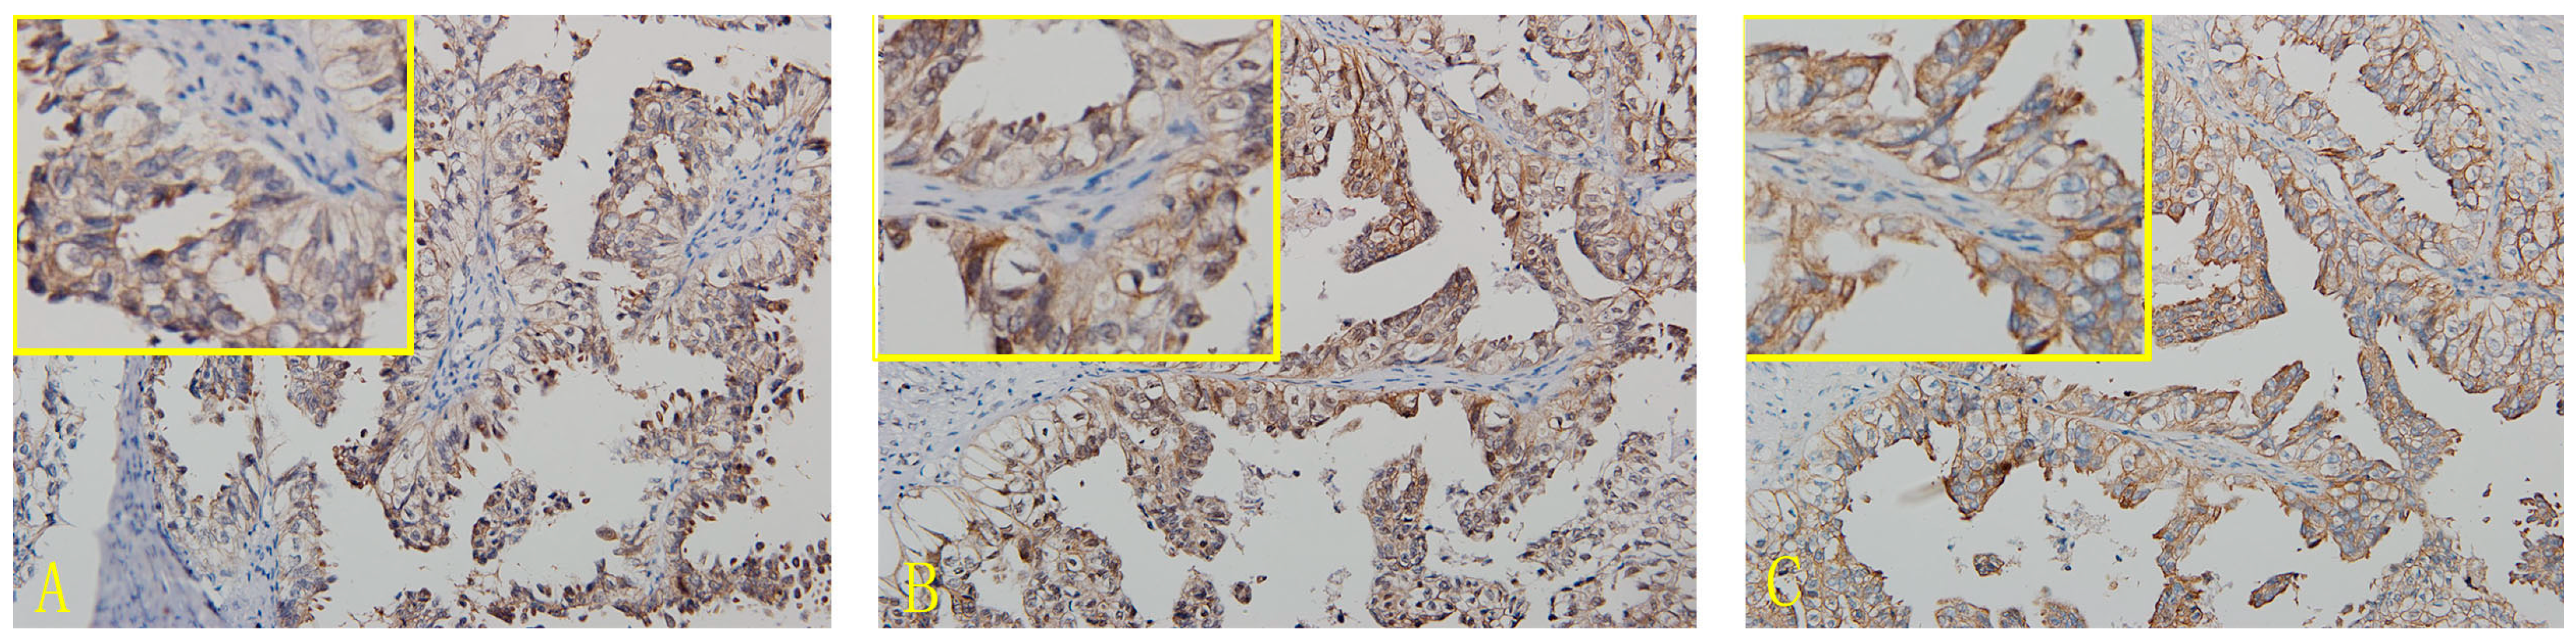

In OCCC tissues, the expression of the CD47 protein was found in the cell membrane and cytoplasm, but mainly in the former. The nuclei were also stained for CD47. The positive expression rate of CD47 in OCCC was 91.9% (79/86). Expression of CD44 was mainly located in the cell membrane, but also found in the cytoplasm, and the positive expression rate of CD44 in OCCC was 90.7% (78/86). c-met protein was mainly expressed in the cell membrane and also found in the cytoplasm. The positive expression rate of c-met was 94.2% (81/86) in OCCC (Figure 1 and Figure S1, Table 1 and Table S1).

Immunohistochemical micrographs of CD44, CD47 and c-met in ovarian clear cell carcinoma (OCCC) (200×). (A) CD44; (B) CD47-OCCC; (C) c-met-OCCC.